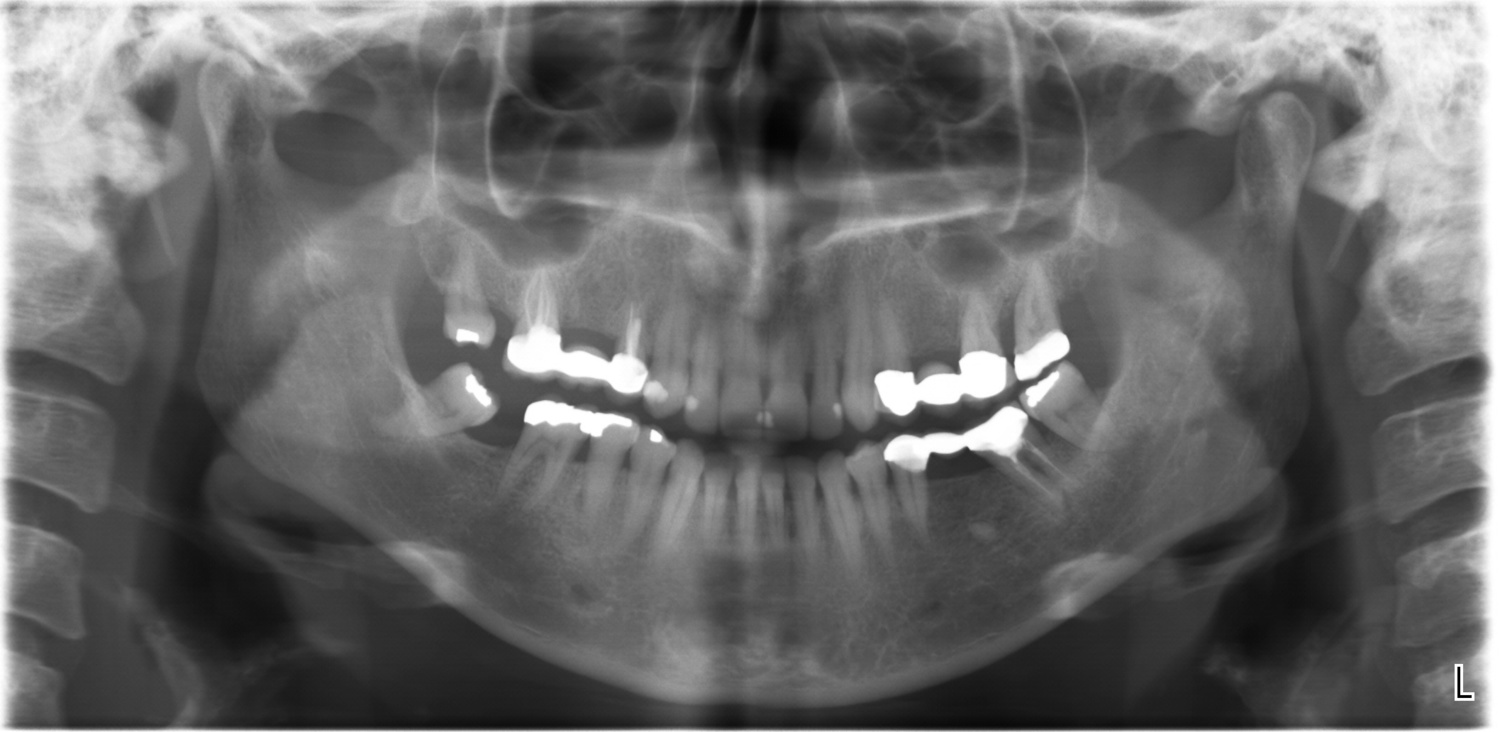

+25 Panoramic X Ray Ideas. In essence, advanced dental imaging can simplify your experience as the manner in which it is conducted is “extraoral”, which means outside of your mouth. They offer a view that would otherwise be invisible to the naked eye.

Thus, it allows you to get a full view of your teeth, gums, jaw, sinuses, palate, tongue, and more. Poye dental imaging software easy to learn & convenient to use, user friendly graphic based interface for 2d image analysis. Powerful & user friendly 2d imaging software.

Powerful & user friendly 2d imaging software. Thus, it allows you to get a full view of your teeth, gums, jaw, sinuses, palate, tongue, and more. 29.the first step in understanding panoramic anatomy is to appreciate the perspective from which each part of the image is presented.

Poye dental imaging software easy to learn & convenient to use, user friendly graphic based interface for 2d image analysis. The dentist is able to not only see the crown and roots of each tooth, but the jaw bones and anatomy surrounding them. This makes it possible for your dentist to notice any of the following problems: